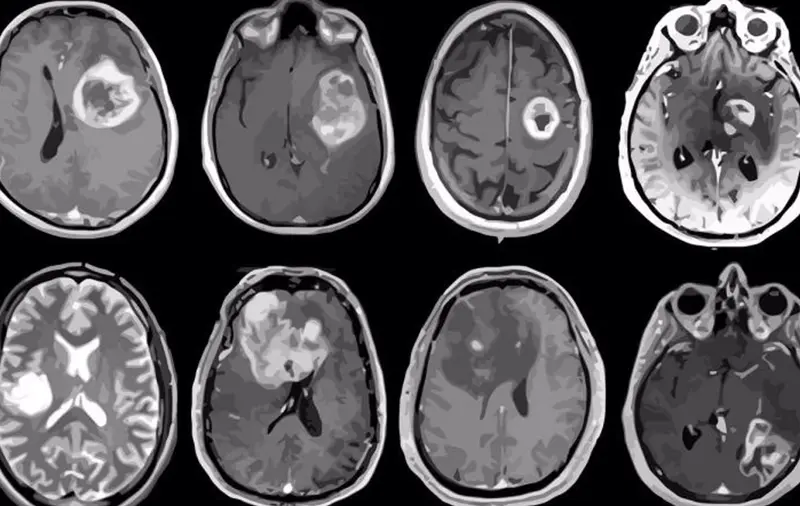

<p> Archivo - Glioblastoma, tumor cerebral agresivo mapeado en detalle genético y molecular. - ALBERT H. KIM - Archivo </p>

Archivo - Glioblastoma, tumor cerebral agresivo mapeado en detalle genético y molecular. - ALBERT H. KIM - Archivo